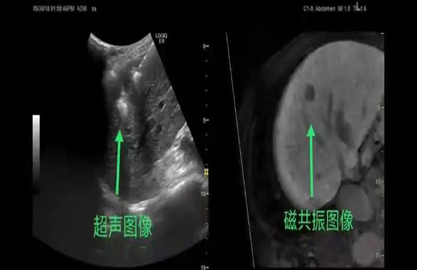

7. 肝脏肿瘤射频消融

B超定位射频消融治疗小肝癌